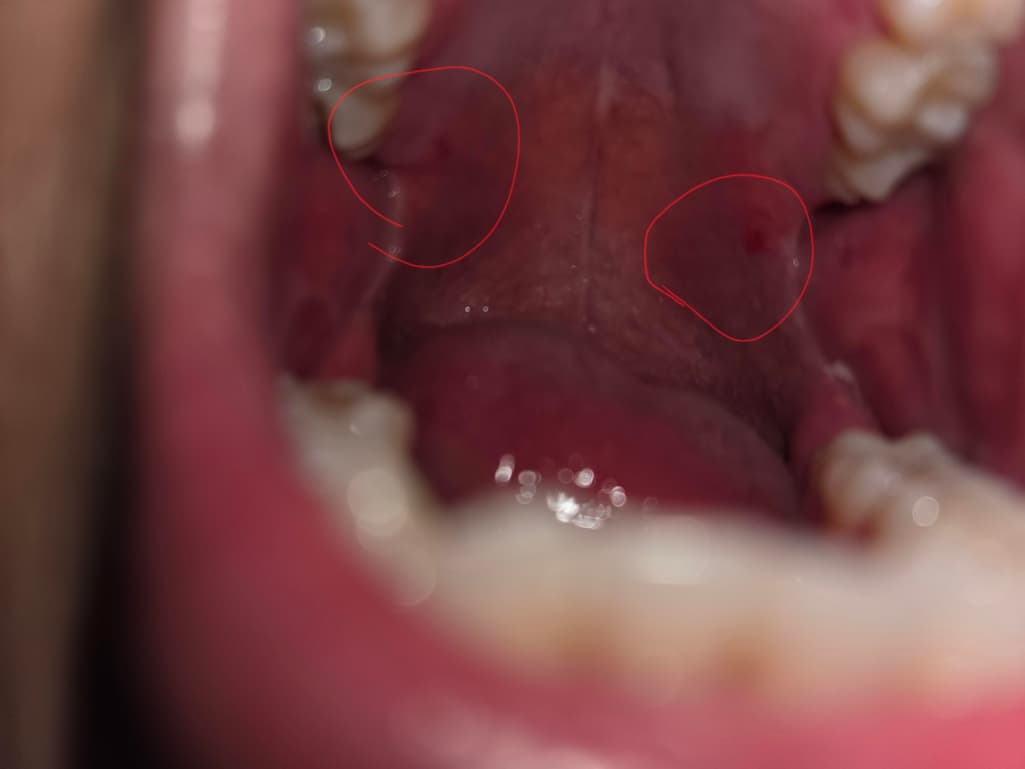

방금 저녁으로 치킨 순살을 먹고 화장실에서 손을 씻고 가래를 뱉었는데 피가 나와서 처음에는 양념치킨의 양념인줄 알았습니다.

혹시나 해서 스마트폰 플래쉬로 확인하니 사진처럼 두 군데가 까졌고 그중 한 군데에서 피가 뱉을때마다 나오네요...

말하신 내용 답변 드리자면 사실 치킨의 양념이나 섬유질이 있는 고기 조각이 입천장이나 편도에 자극을 줄 수 있어서, 이를 물어먹거나 씹을 때 가벼운 찰과상이나 작은 상처가 생길 수 있습니다. 이로 인해 피가 나는 것일 가능성이 큽니다.

편도가 까졌다고 하셨는데, 이는 일시적인 찰과상일 수 있으며, 특별한 치료 없이 자연히 회복될 가능성이 높습니다. 다만, 만약 상처 부위에서 피가 계속 나오거나, 통증이 심해지거나, 부종이 생긴다면 감염의 징후일 수 있으므로 병원을 방문하여 치료를 받는 것이 좋아요

현재로서는 상처 부위를 너무 자주 자극하지 않도록 주의하고, 자극적인 음식이나 뜨거운 음료는 피하는 것이 좋습니다. 구강청결제를 사용하거나 따뜻한 소금물로 헹구는 것이 도움이 될 수 있습니다.

증상이 지속되면 병원에 가서 확인하는 것이 더 안전합니다